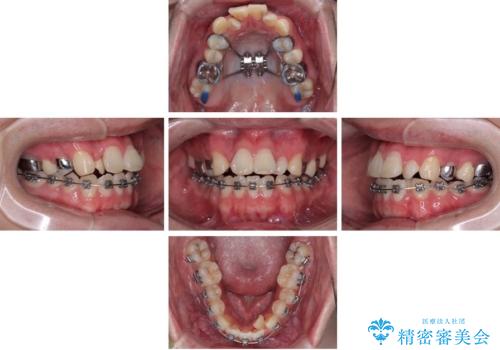

治療方針

このような歯列の狭さに起因するデコボコを改善するために、**MARPE(骨に固定する上顎急速拡大装置)**を使用して、上顎の横幅を拡大し、これにより歯が並ぶためのスペースを確保し、メタルブラケットを用いて歯列を整えていく計画としました。

費用面を考慮し、装置はコストパフォーマンスに優れたメタルブラケットを選択。見た目よりも機能と効果を重視したい方には特におすすめの選択肢です。